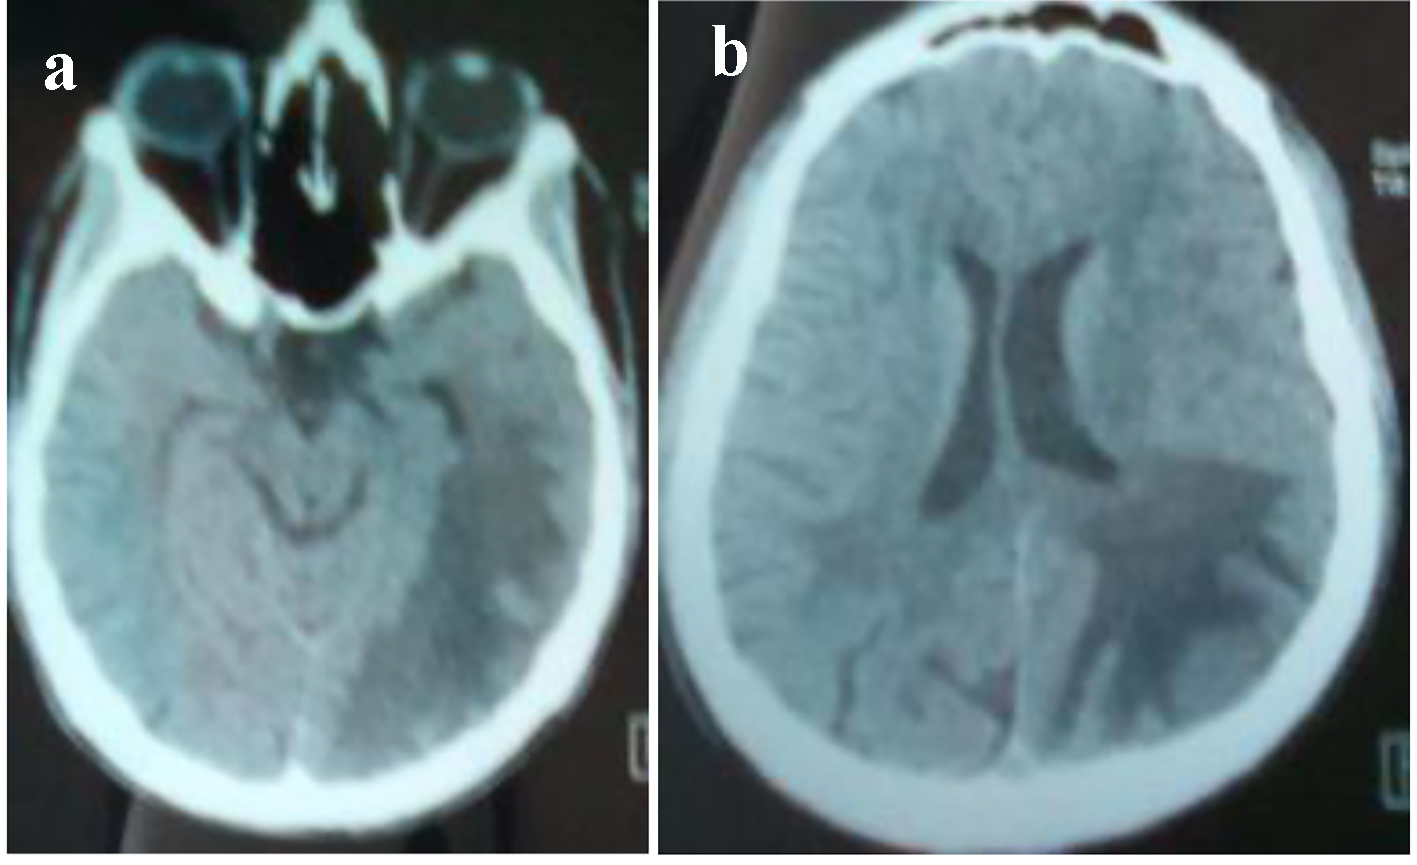

Figure 4. (a, b) Brain CT: hypodensity in left cortico and under cortical parietooccipital area and in the white matter of the right centrum semiovale.